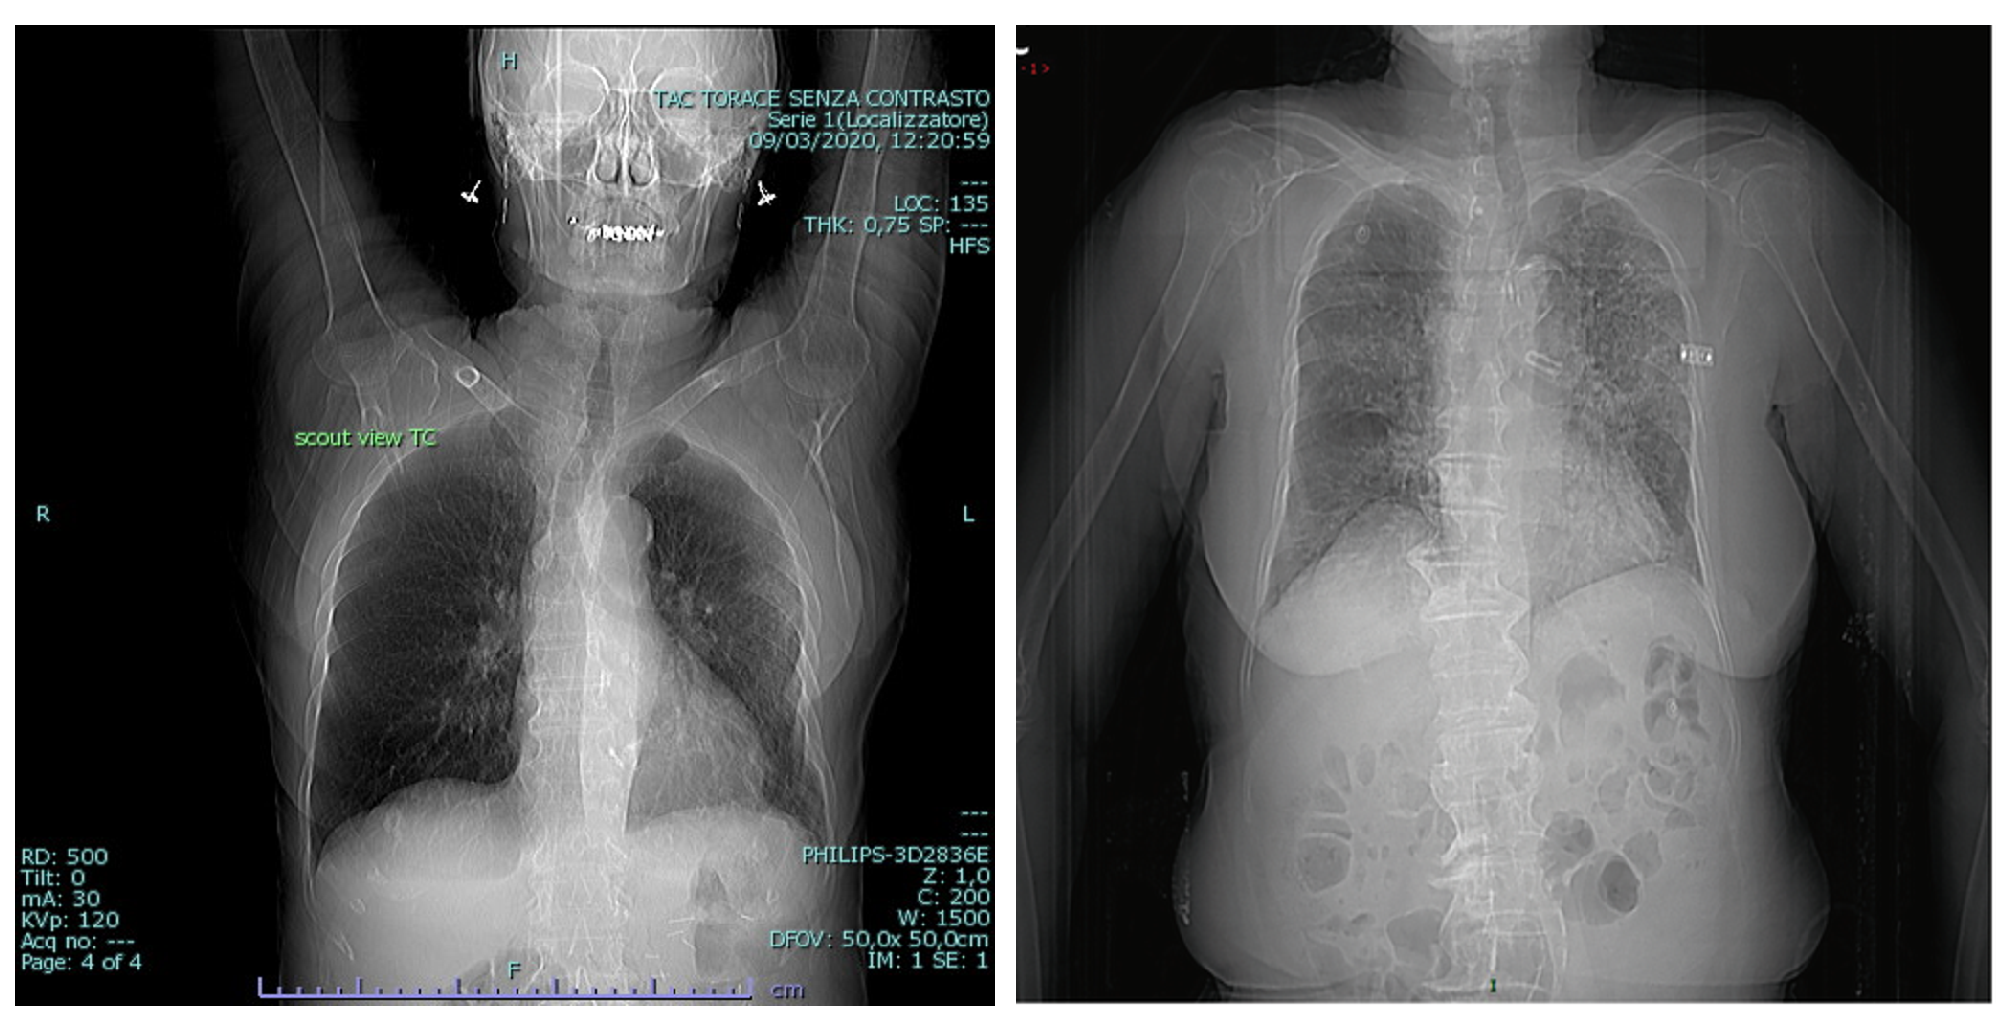

3.3. BIMCV COVID19+

3.4. RSNA

3.6. Montgomery County X-ray

3.7. Shenzhen Hospital X-ray

3.8. National Institute of Health (NIH)